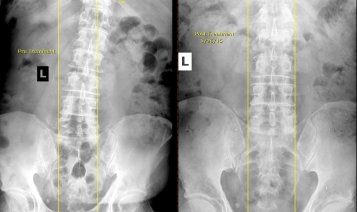

Pre & Post X-Rays

X-rays allow us to create an image of the skeletal system, thereby providing chiropractors with a better understanding of your body.